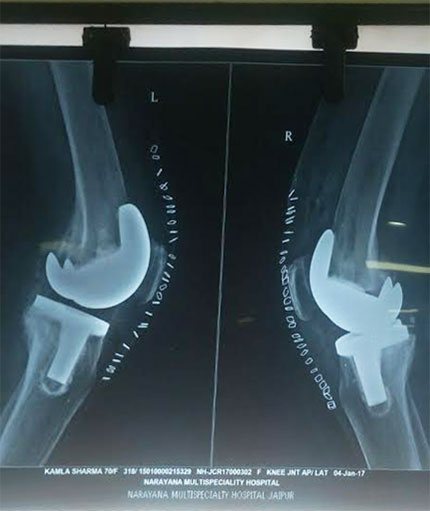

Knee Replacement

Knee replacement surgery otherwise knee arthroplasty, is a surgery involving the replacement of the damaged, diseased or distorted joint surfaces of the knee, with a prosthesis. As per the condition of the patient’s knees, the surgery can be performed as a partial knee replacement surgery or the total knee replacement surgery.